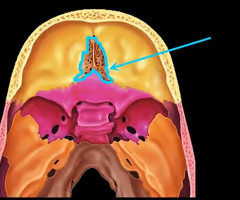

Cribriform plate of the ethmoid bone (notice olfactory formina in it - for olfactory nerves. Crista galli “rooster’s comb” dura mater attaches here)

Perpendicular plate of the ethmoid bone (helps form bony nasal septum with vomer)

Optic canals (optic nerve)

Optic canals (optic nerve)